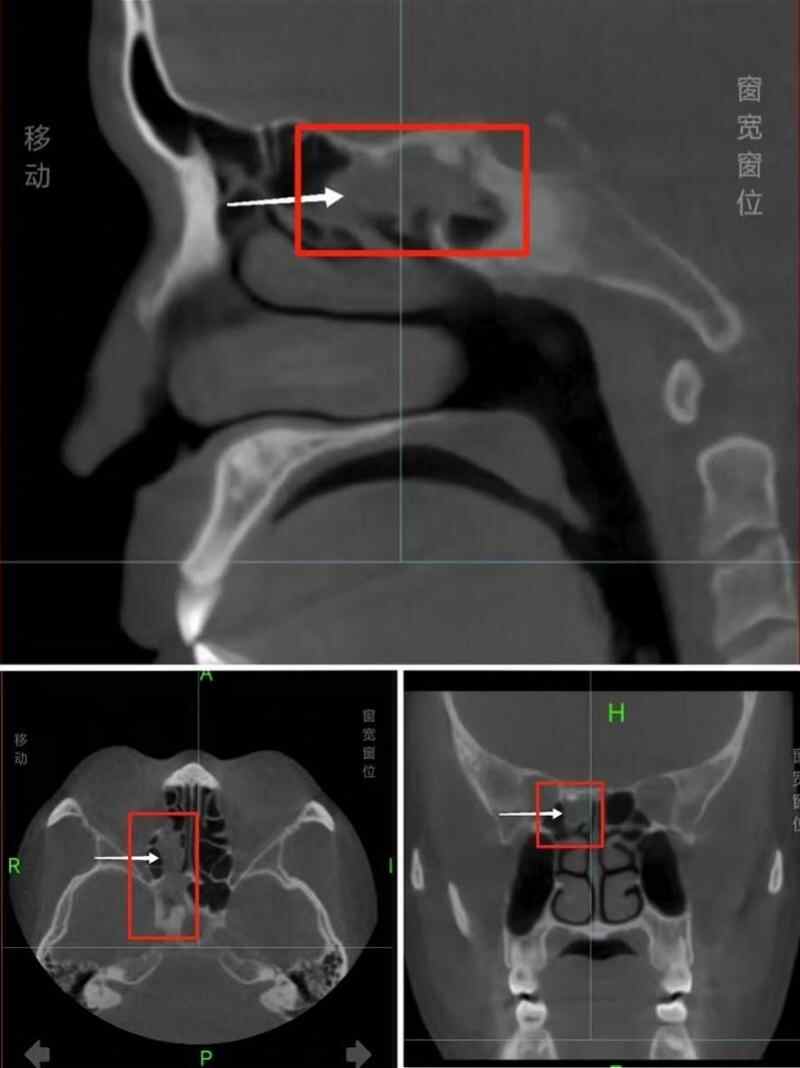

CT结果显示:阿杰的右侧蝶窦存在占位性病变。存在一个性质待查的“骨瘤”,并同时诊断出右上颌窦囊肿、右侧筛窦、蝶窦炎、鼻中隔偏曲及鼻炎。唐医生告诉阿杰,蝶窦内的这个“异物”不一定是骨瘤,也可能是其他东西,但无论是什么,想彻底解决问题,必须通过手术探查清楚。同时,长期的异物存在已导致局部炎症和反复头痛。考虑到多年饱受困扰,阿杰选择了手术。

鼻内镜微创手术由张庆丰主任、李丽明主任医师指导,唐志元副主任医师完成。当唐医生打开阿杰右侧后组筛窦,小心翼翼地探查后,这个令人震惊的“异物”呈现在大家面前:取出的并非预想的骨瘤,而是一截长约3厘米、质地坚硬的树枝!

术后看到取出的异物,阿杰恍然大悟!这截树枝,正是2007年那次意外受伤的“遗留物”。当年县医院处理时虽然取出了几块碎片,但这截“狡猾”的树枝,很可能在伤口感染、脓肿、崩线的复杂过程中,“躲”进了位置深在、结构复杂的右侧后组筛窦及蝶窦腔内。这截树枝竟如“隐形”般藏匿了整整18年……